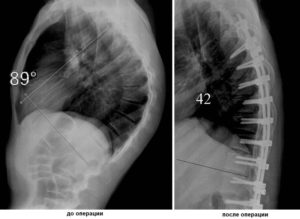

Если такими способами остановить прогрессирование болезни не удается, и угол изгиба превышает 70 градусов, показана операция на позвоночнике. Также хирургическое вмешательство оправдано при непрекращающемся болевом синдроме, серьезных нарушениях кровообращения, резком ухудшении работы органов дыхания. Выравнивание позвонков происходит за счет вживления специальных металлических конструкций.

К оперативному лечению прибегают при выраженном кифозе с углом более 60º, компрессии спинного мозга, стойком болевом синдроме. При этом возможно установление поддерживающих конструкций (мост) с частичной коррекцией искривления позвоночника, удаление грубо измененных позвонков и дисков.

Оперативное лечение требуется в ситуации, когда угол кифоза достигает 75 градусов. Кроме того, показаниями к операции выступают стойкий болевой синдром, не поддающийся купированию консервативными методами лечения, а также нарушение функций органов грудной клетки.

Хирургическое лечение болезни Шейермана-Мау предполагает выпрямление и укрепление позвоночного столба с помощью специальной металлической конструкции.